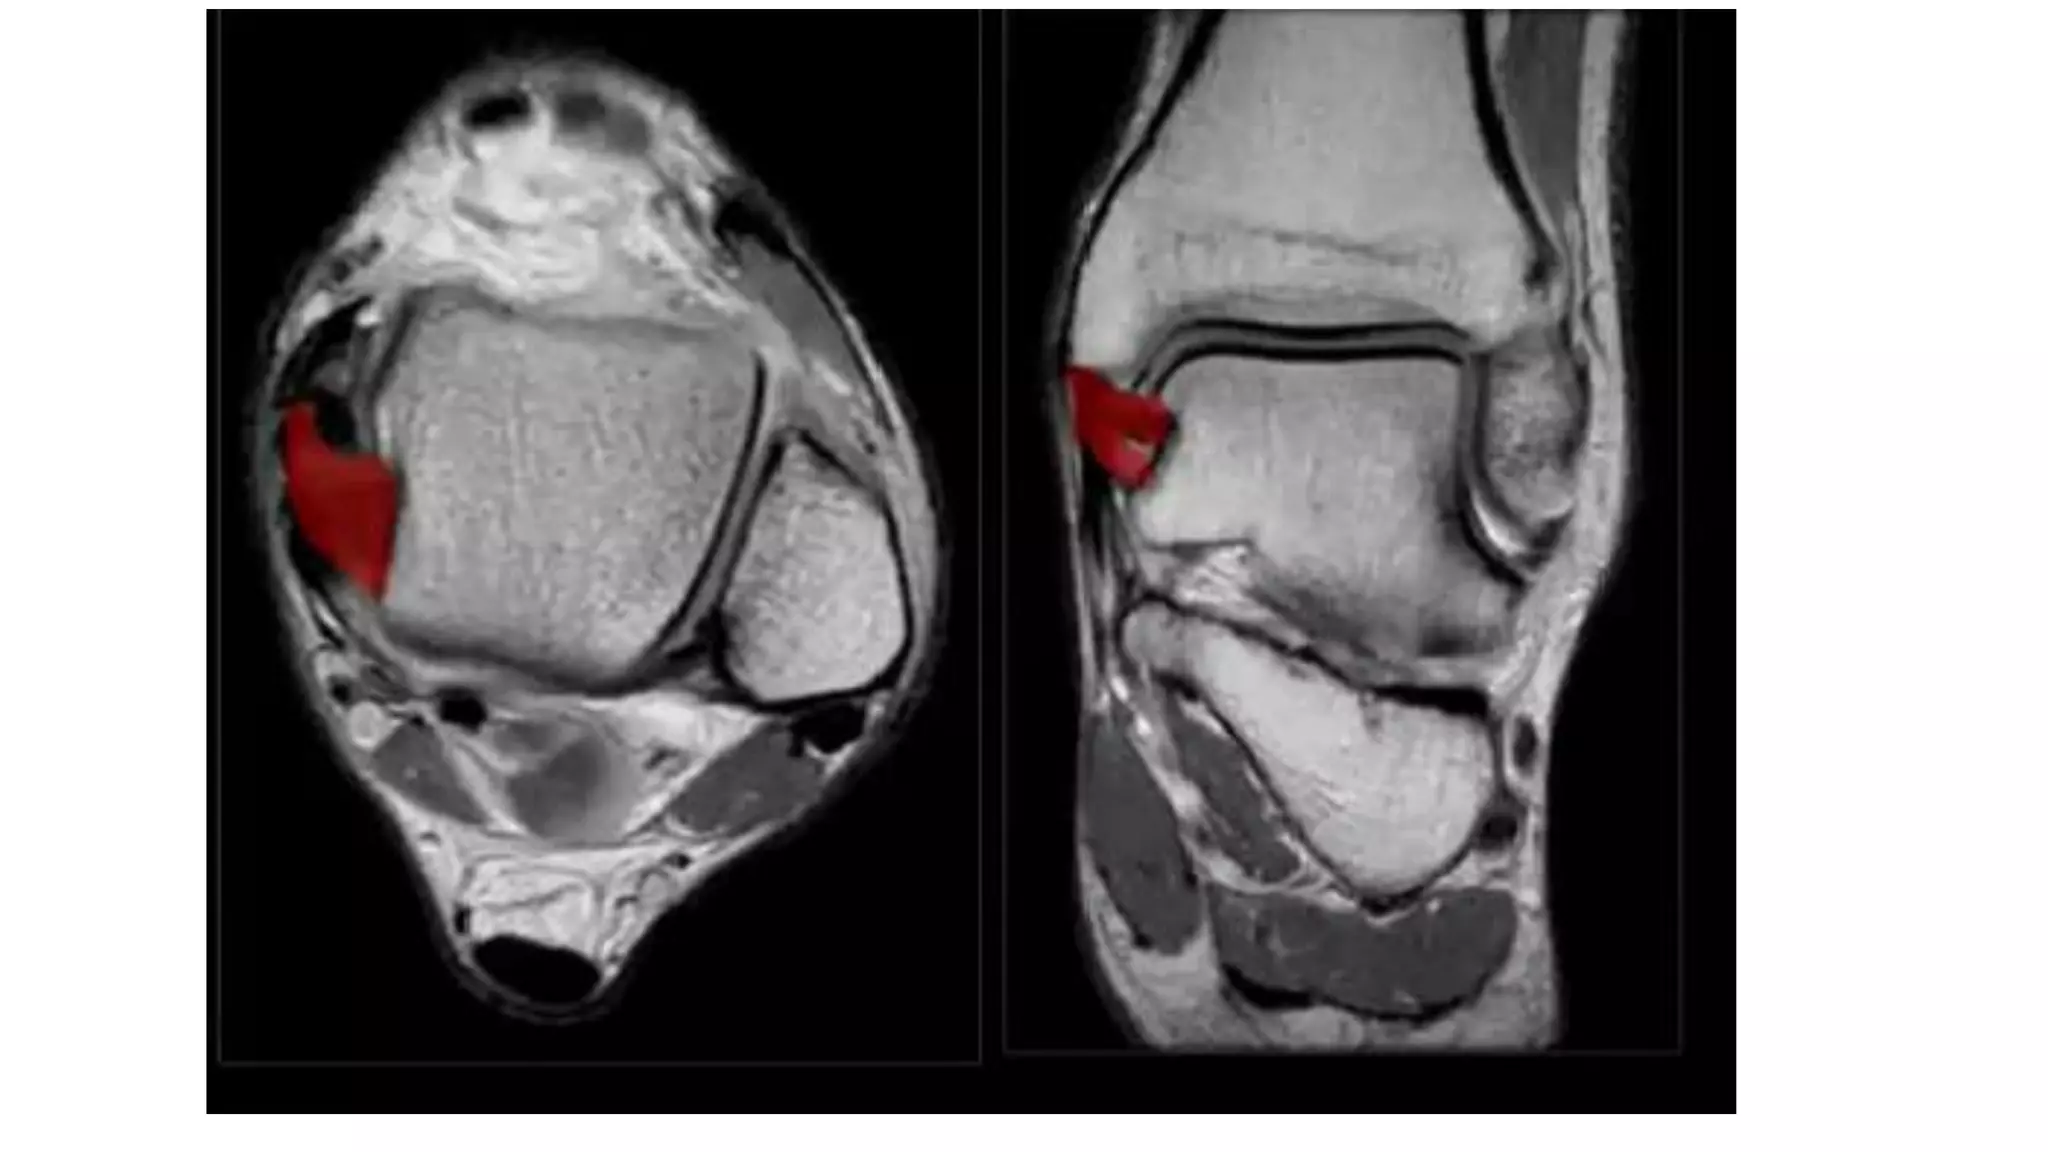

This MRI ankle report describes the anatomy of the ankle, including ligaments such as the anterior and posterior tibiofibular ligaments, syndesmosis ligaments, deltoid ligament, and calcaneofibular ligament. It outlines the tendons in the anterior, lateral, medial, and posterior compartments, including the tibialis posterior, peroneus, flexor hallucis longus, and Achilles tendons. The sinus tarsi is also noted.